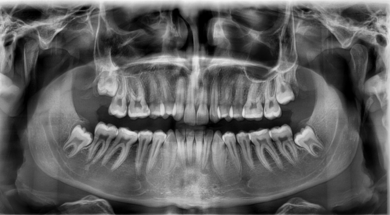

OPG یا عکس پانورامیک

این تصویر یک نمای کلی از همه دندونها و ریشه ها به ما میده. وجود دندان نهفته، دندان غایب، مشکلات ریشه، کیست یا ضایعات وسیع در این عکس مشخص میشه. برای تمام بیماران ارتودنسی، OPG اولین و پایه ای ترین تصویر تشخیصی هست.